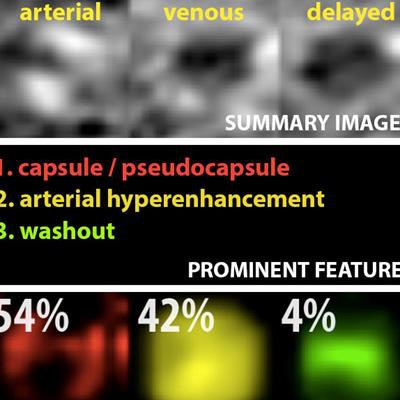

Example output of the Yale group's patent-pending "explainable" deep-learning system. In addition to providing a prediction (e.g., hepatocellular carcinoma), an explainability algorithm justifies the system's decisions with radiological features, feature maps, and relevance scores that contributed to its analysis. Image courtesy of Dr. Julius Chapiro.

Example output of the Yale group's patent-pending "explainable" deep-learning system. In addition to providing a prediction (e.g., hepatocellular carcinoma), an explainability algorithm justifies the system's decisions with radiological features, feature maps, and relevance scores that contributed to its analysis. Image courtesy of Dr. Julius Chapiro.The 494 liver lesions included six liver lesion types: simple cysts, hemangioma, focal nodular hyperplasia, HCC, intrahepatic cholangiocarcinoma, and colorectal carcinoma metastasis. These lesions were defined on T1-weighted MRI scans (arterial, portal venous, and delayed phase) and were divided into a training set of 434 lesions and a test set of 60 lesions. Next, the group compared the algorithm's performance on the test set with that of two board-certified radiologists.

The deep-learning algorithm achieved an overall accuracy of 92%, compared with 80% to 85% for the experienced board-certified radiologists, according to Wang.

Notably, the system also achieved 90% sensitivity for classifying HCC, compared with an average sensitivity of 65% for the two radiologists.